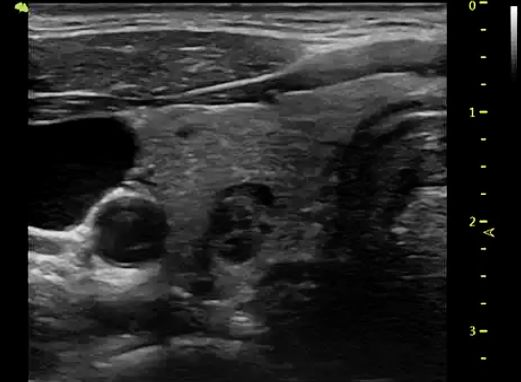

利用高分辨率超声检查甲状腺结节以明确结节大小、形态、位置、个数、回声,内部和周边血流信号及邻近重要的器官结构、可疑的颈部淋巴结。

▲甲状腺结节的超声成像